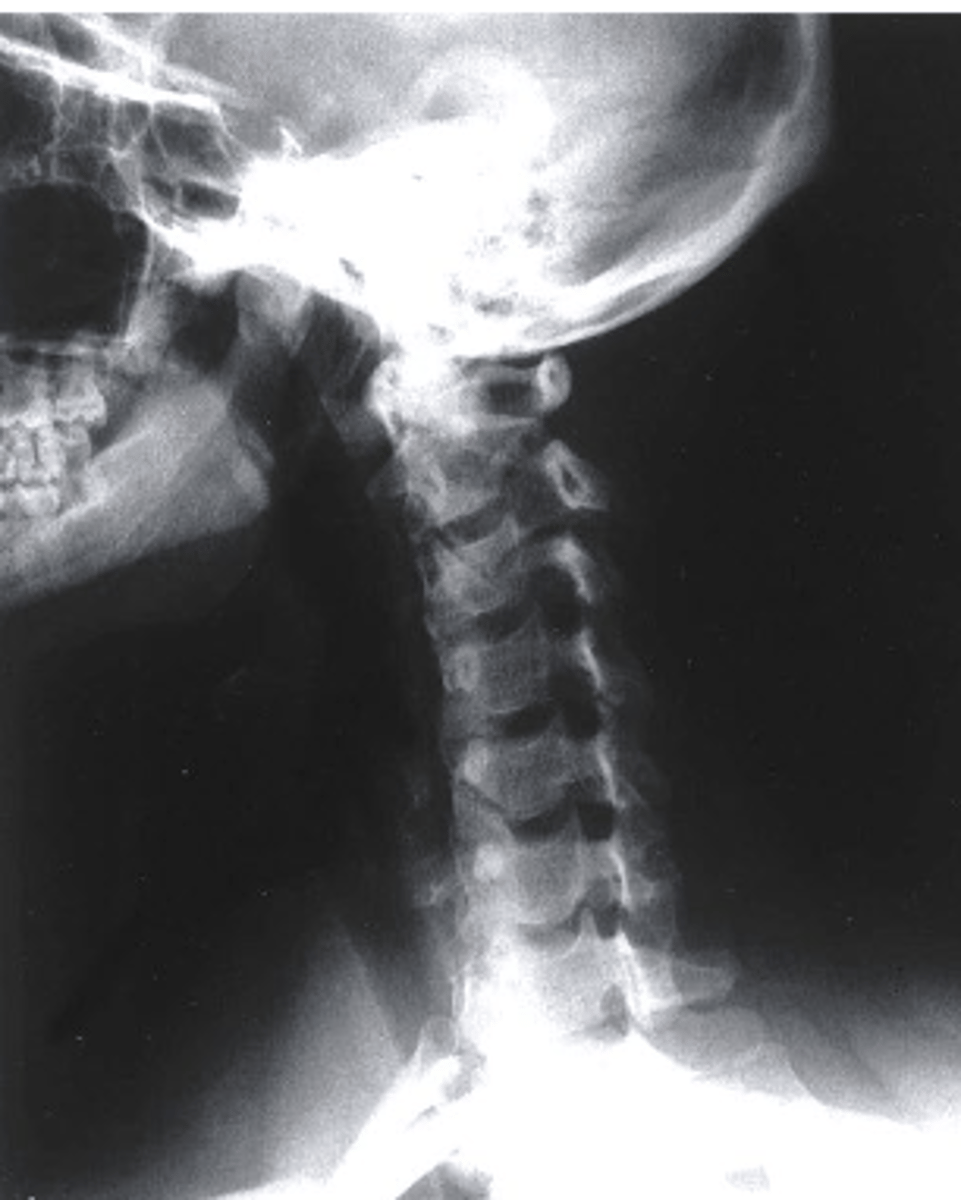

Lateral

What view is being captured on this patient?

a. AP Lower C Spine

b. Oblique

c. Lateral

d. PA Lower C Spine

what can be identified on a lateral view of the C spine?

-arches of C1

-Dens

-vertebral bodies of C2-C7

-articular pillars and lamina

-IVD spaces from C2-C3 through C6-C7

-spinous processes

-transverse processes

-facet joint surfaces